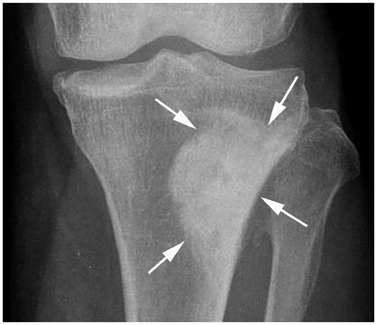

Systematic Approach of Sclerotic Bone Lesions Basis on Imaging Findings

- Sclerotic bone lesions are common, but there are diverse groups of tumors and non-tumorous lesions. Although plain radiograph and computed tomography can reveal important characteristics of these lesions, diagnosis is often challenging for radiologists. A systematic approach and familiarity with the imaging features of various sclerotic bone lesions may be greatly helpful for eliminating in the differential diagnosis. This review describes the systematic approach to diagnosing sclerotic bone lesions based on imaging findings.